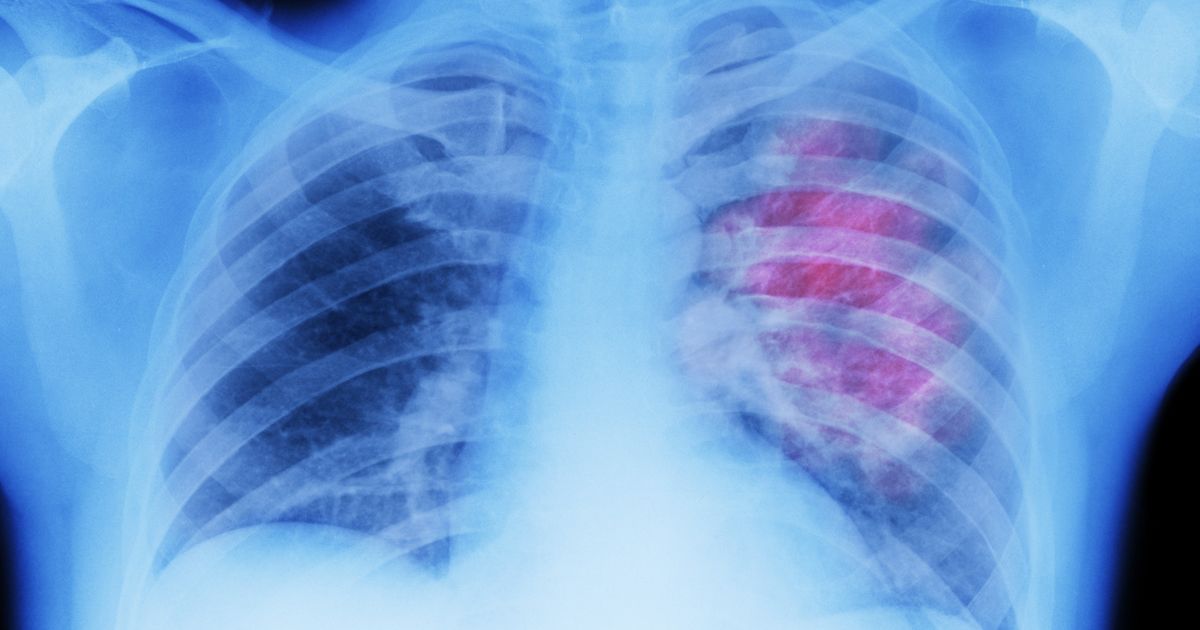

Lung Cancers

Lung cancers are serious conditions that cause the cells in the lungs to divide at an uncontrollable rate. When these cells divide, tumors will grow and reduce a patient's ability to breathe properly. As with most cancers, early detection can greatly increase a patient's chances of effectively treating it. However, the symptoms associated with lung cancer often appear similar to the symptoms attributed to a respiratory infection, which can make early detection difficult. While it's possible for anyone to develop cancer in the lungs, high amounts of exposure to smoke as well as cigarette smoking will substantially increase the likelihood individuals develop lung cancer. Some of the first symptoms patients may notice with lung cancer include unexplained weight loss, chest infections, appetite loss, and shortness of breath. There are four stages of lung cancer, labeled as I, II, III, and IV. The fourth stage is the most severe and occurs when the cancer has spread to other areas of the body.